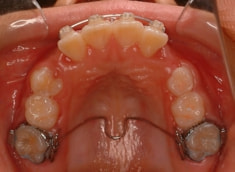

治療前

治療後(12ヶ月後)

治療開始時

治療開始から約3ヶ月後